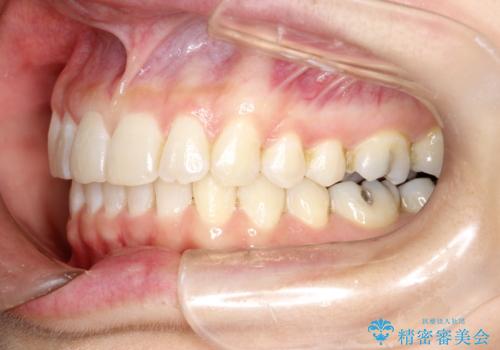

- 前歯のがたつきを気にされて来院されました。

右上の前から2番目の歯が前方に大きく傾いており、下の前歯もガタガタしていました。

インビザラインにて、歯と歯のあいだをわずかに削り並べる計画としました。

しっかりとマウスピースを使用していただけたので、順調に治療を終えることができました